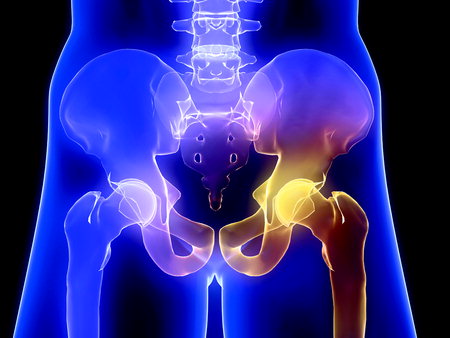

고관절은 흔히 엉덩이 관절이라고 불리며, 골반 쪽에 위치한 공-소켓(ball-and-socket) 형태의 관절입니다. 둥근 모양의 대퇴골두가 오목한 비구(acetabulum)에 맞물려 있어 골반과 허벅지를 연결하는 역할을 합니다.

이 관절은 체중을 지탱하고 보행, 달리기 같은 다리의 움직임을 가능하게 하는 핵심 구조입니다.